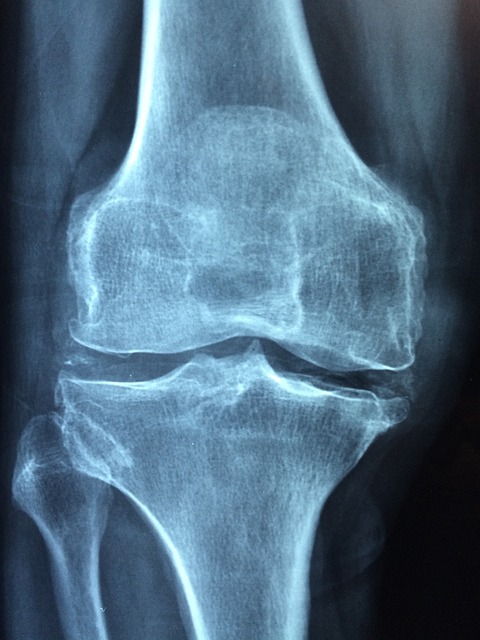

- 양쪽 손목, 양쪽 무릎과 같은 대칭적인 관절에서 통증이 발생합니다.

류마티스 관절염의 치료법

류마티스 관절염은 완치가 어렵지만 조기 치료를 통해 증상을 완화하고 관절 손상을 최소화할 수 있습니다.

수술적 치료

- 관절 변형이 심한 경우 인공관절 치환술과 같은 수술을 고려합니다.